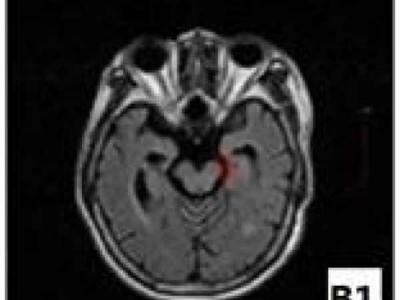

脑梗死患者为何出现偏瘫肢体运动功能恢复

磁共振检测显示,运动诱发电位阴性脑梗死患者患侧大脑脚面积于病后6个月时已经出...

从静息态脑功能网络揭示老年痴呆的发生

早期轻度认知障碍和晚期轻度认知障碍患者静息态脑功能网络中中间中心度存在差异的...